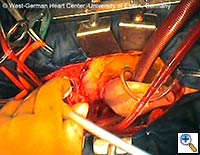

|

|

|

| Figures 4–6. These figures demonstrate advancement of the prosthesis over a transfemorally placed guide wire, the most secure method to assure appropriate placement. | ||

- The E®-vita prosthesis is then inserted into the descending aorta, with or without the accompanying guidewire. In particularly difficult descending aortic anatomy, a guidewire may be passed transfemorally, preferably via a previously inserted sheath. In some centers, the guide wire is a mandatory adjunct to secure the graft into the true lumen for aortic dissection and to avoid thrombus mobilization for aneurysms. (see Figs. 4-6 for placement over guide wire)